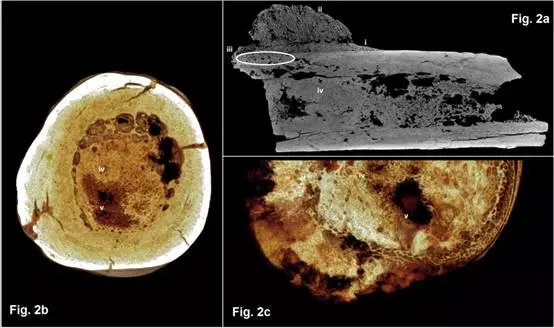

化石样品中的病变部位图(图2a和图2b)与现代临床骨肉瘤样品图(图2c)

该化石样品是左脚上的第五跖骨,含近端骨干和远端部分,无脚关节。研究人员在该化石的成骨骼表层发现了一处不规则的半球状组织块。样品横截面成像显示,该半球状组织块并没有完全与骨表层融合或者嵌入其中,而是附着在骨骼表面,形成不规则的海绵状编织骨纹理结构,其外貌看起来像菜花。该半球状组织块正下方的皮质骨被一薄层新生编织骨覆盖,形成颗粒状纹理结构,在横向视图中,显示出椭圆体溶解病变的特征。出人意料的是,显微CT成像显示骨髓腔的大部分空间充满骨质,表明其内部结构发生重塑并重新形成新骨。鉴于髓腔是正常造血骨腔的一部分,这意味着这些骨质是一种侵略性的成骨状态,即癌症。

鉴于化石样品内部与外部的形态学特征,及其与现代临床诊断的股骨远端骨肉瘤的比较,该化石样品中的病变似乎最有可能是骨肉瘤。骨肉瘤是一种原发性癌症,通常会引起骨骼表层和髓腔的破坏并造成其一定程度的矿化。